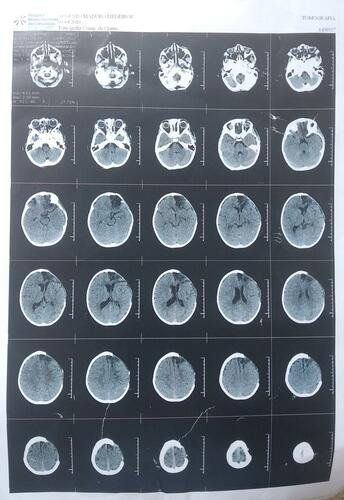

No dia 07/01/2022, o Augusto, eu e minha filha fomos vítimas de um acidente de carro, em que um caminhão entrou na contramão e bateu de frente no nosso carro. Graças à Deus, todos sobrevivemos, mas o Augusto, mesmo estando na cadeirinha, sofreu traumatismo cranioencefálico (TCE) grave devido ao forte impacto. Isso causou a quebra de uma parte do crânio dele, necessitando que parte do crânio fosse removido. Ele ficou com algumas dificuldades motoras, mas o nosso principal medo é de que algo possa acontecer pela falta da proteção do cérebro, visto que é um risco grande.

Hoje o Augusto já está andando e falando muito melhor. Desde o dia que saiu do hospital, graças às intensivas sessões de fisioterapia, voltou a sentir muito mais confiança ao andar. Contudo, para que ele possa voltar a poder ir para escolinha e ter uma vida normal, ele ainda necessita realizar a cranioplastia. O procedimento irá recuperar esta parte do crânio que foi retirada devido ao acidente.

A cirurgia não foi feita antes em função da necessidade dele atingir mais peso, tamanho e esperar alguns meses após o traumatismo, conforme orientações médicas.